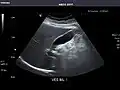

Liver

Ultrasonography of the liver with some standard measurements[6]

In patients with deranged liver function tests, ultrasound may show increased liver size (hepatomegaly), increased reflectiveness (which might, for example, indicate cholestasis), gallbladder or bile duct diseases, or a tumor in the liver.

Liver: Diffusely homogeneous and normal in echogenicity. No focal mass or contour nodularity. No intrahepatic biliary ductal dilatation.